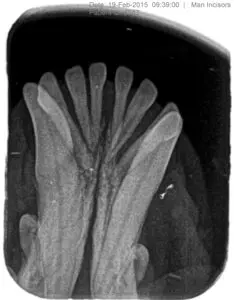

The most common teeth we see that require extraction are the mandibular and maxillary incisors, followed by the maxillary premolars. This is anecdotal, although I have been practicing dentistry since the advent of running water and flushable toilets! The reason these teeth are involved is that they (especially the incisors) are overly crowded, while also not being used to chew. Incisors are meant to be used to grab things, not chew. The incisive bone associated with these teeth is thin and not as dense as the bone that lies behind the canines.

Advanced bone loss on the mandibular incisors requiring surgical extraction